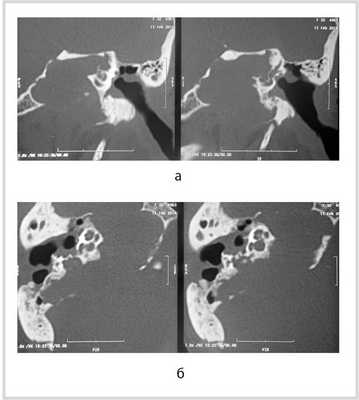

Рис. 1. КТ височных костей пациентки М. а — коронарная проекция: деструктивная полость в пирамиде височной кости, заполненная субстратом неоднородной плотности, капсула лабиринта значительно разрушена на уровне базального и апикального завитков улитки, латерального и верхнего полукружных каналов; б — аксиальная проекция: деструктивная полость с разрушением задней грани пирамиды, передневерхней и нижней поверхности.

По результатам МРТ/РКТ височных костей: левая височная кость тотально заполнена патологическим субстратом с поражением пирамиды. Имеются деструктивные изменения височной кости: задняя грань пирамиды разрушена на протяжении 10 мм, передневерхняя — протяженностью до 15 мм, нижняя поверхность — до 25 мм. Капсула лабиринта значительно разрушена на уровне базального и среднего завитков улитки. Костная стенка лабиринтной части канала лицевого нерва не прослеживается, стенка тимпанального и мастоидального отделов сохранена. Отмечалось разрушение стенки канала внутренней сонной артерии. После внутривенного контрастирования не было отмечено деформации стенки сосуда.